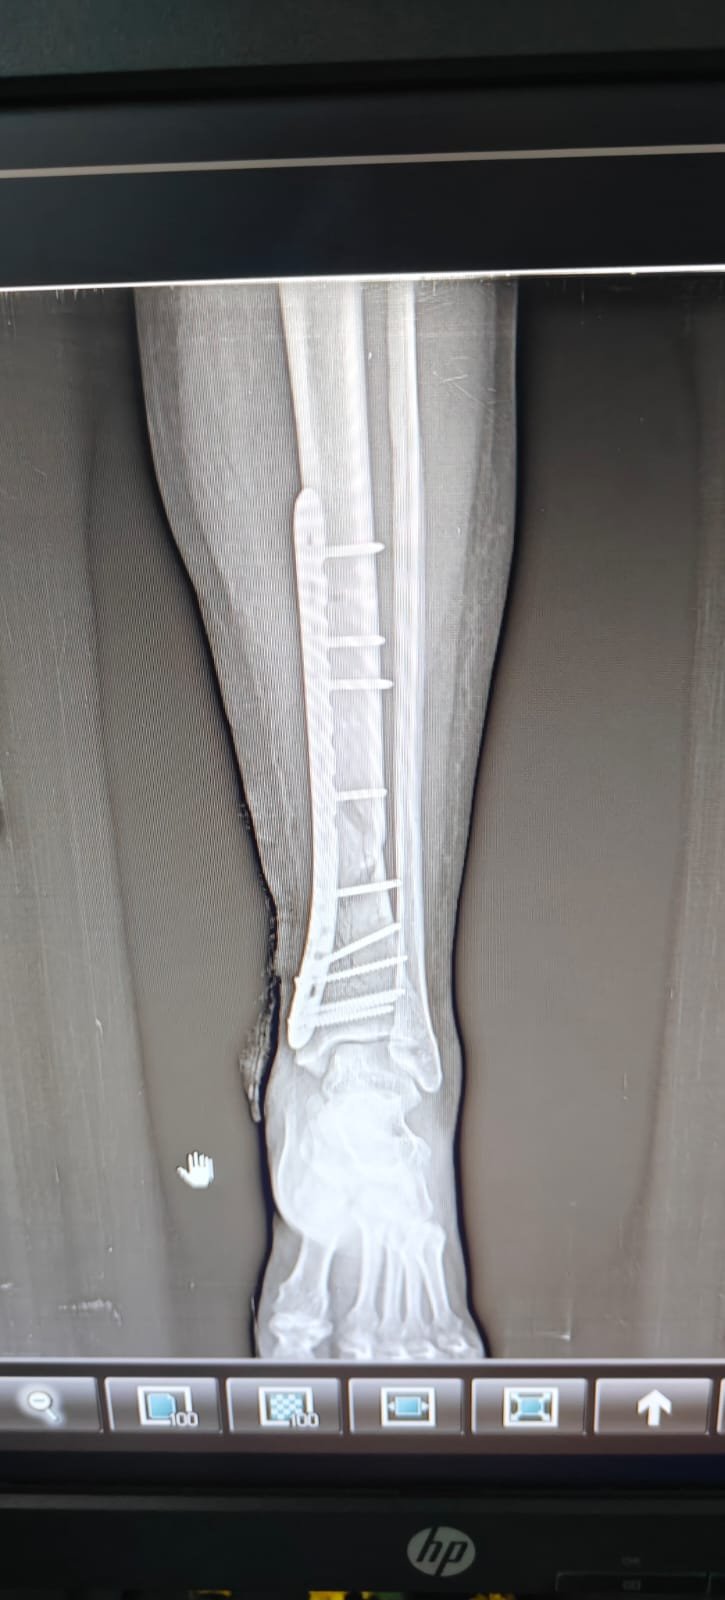

- Fracture Treatment